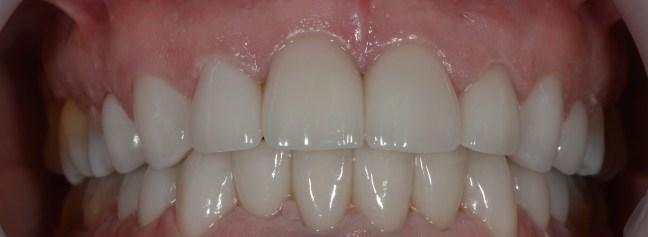

Kozmetikai kezelés: régi tömött, szuvasodott frontfogak szanálása, koronával történő leplezése.

A választott korona típusa: E-max préskerámia (fémmentes) szóló koronák.

A választott fogszín: A1 .

A protetikai munka elkészülésének ideje: 5 munkanap.